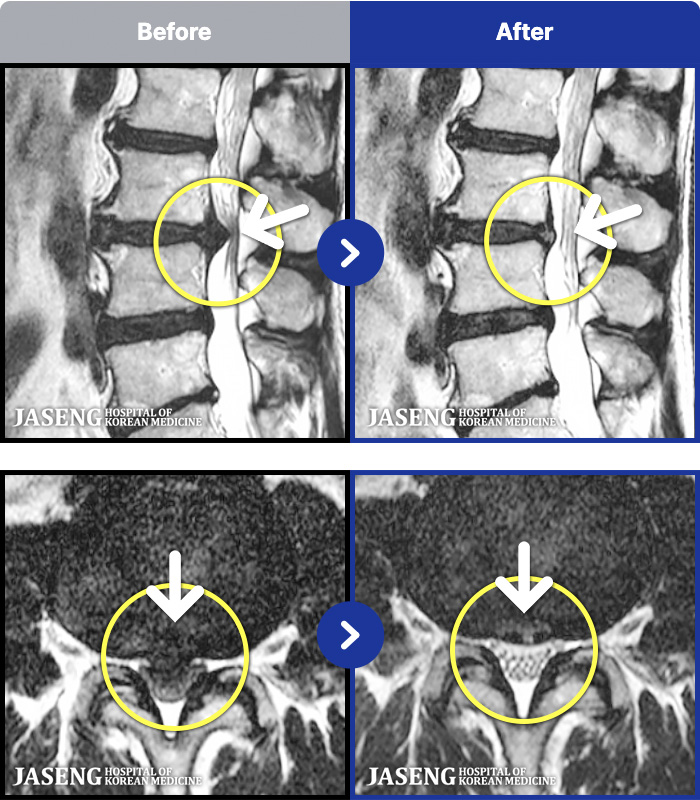

- MRI ġ

MRI ġ

191 MRI ũ ʸ Ȯϼ.

[Կñ:22.07.16~26.03.17]

[_㸮ũ] 㸮 ٸ ϰ ϻȰ Ұ߽ϴ.